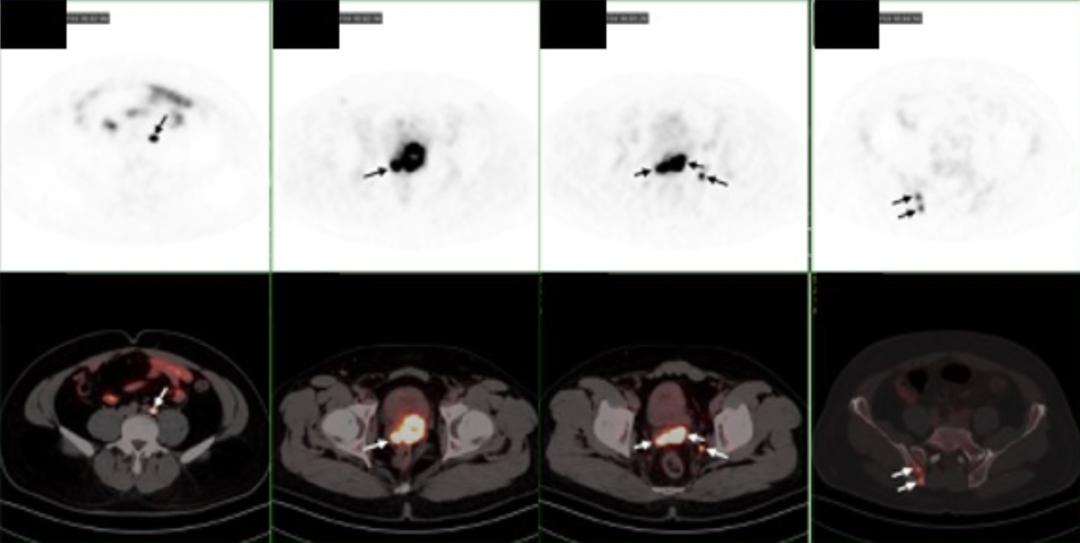

患者为43岁中年男性,初诊PSA 54 ng/mL,穿刺病理为前列腺腺泡腺癌(Gleason 5+5)。MRI显示侵犯精囊、直肠,盆腔及腹膜后多发淋巴结转移。PSMA PET/CT显示前列腺弥漫性PSMA高表达,骶前、腹膜后及两侧髂血管淋巴结转移,双侧髂骨局灶性PSMA高表达。

在3周期PSMA核素治疗后,患者复查PSMA PET/CT提示:前列腺右侧外周带局灶PSMA表达略增高,左侧精囊腺局灶性PSMA高表达相仿。髓前、腹膜后及双侧骼血管淋巴结退缩,髂骨未见PSMA表达增高,考虑活性受抑。

叶定伟教授表示:“我们与Peter Mac癌症中心方案的主要区别在于,在PSMA核素治疗的基础上联合了新型内分泌治疗,患者采用这种联合治疗后的影像学退缩非常明显,PET/CT显示治疗后前列腺病灶活性显著降低、骨病灶活性受抑、淋巴结退缩;PSA由初诊的53.7 ng/mL降低至术后0.01 ng/mL;病理检测进一步证实了这种治疗方案显著效果——仅有1%的瘤荷残存并且切缘阴性。”